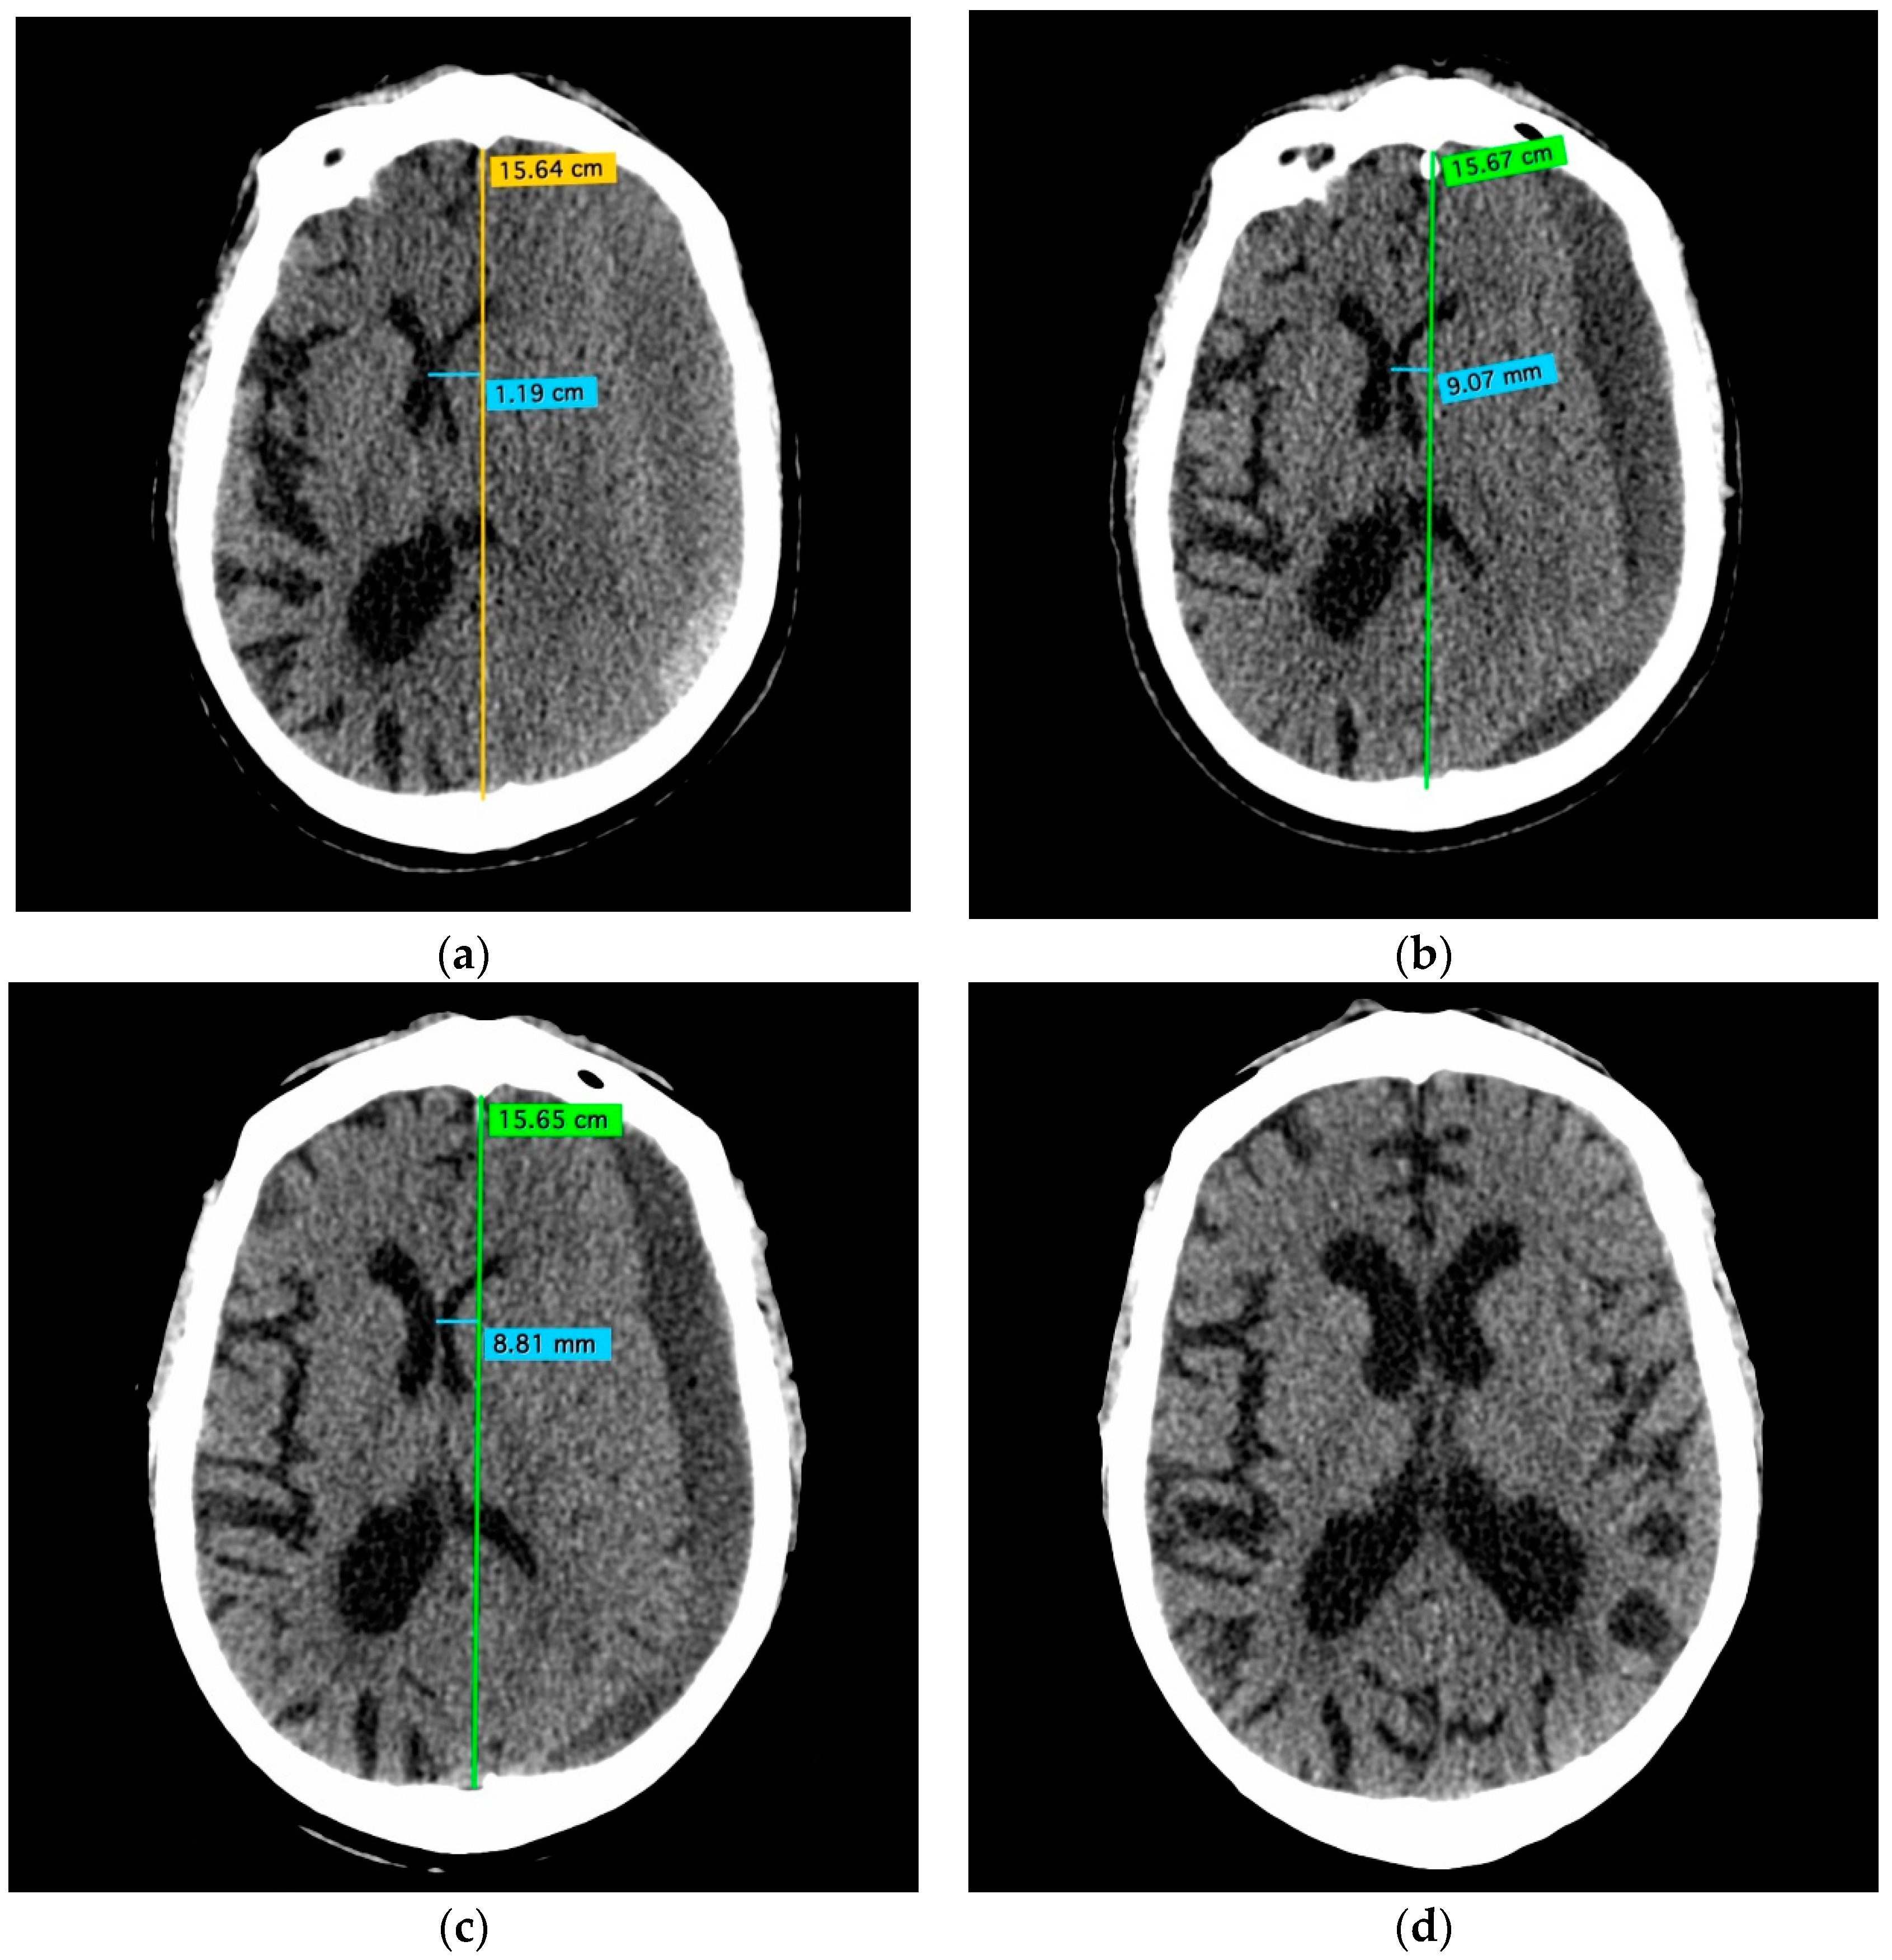

- A 70-year-old patient with left-handed CSDH and a midline shift of 12 mm, motor aphasia, and right-hand hemiparesis.

- A 42-year-old patient with bilateral CSDH that progressively increased during 1.5 months from 54 mL to 69 mL on the right-hand side and from 68 mL to 83 mL on the left-hand side, causing significant compression of both hemispheres and neurological deterioration.

- An 89-year-old patient with bilateral CSDH (no midline shift). There was no apparent connection with an antecedent head injury. However, the patient’s relatives reported that the patient did periodically fall. At the time of admission, the patient presented tetraparesis and a decreased level of consciousness.

3.2. CSDH Volumes

3.3.2. Efficacy Endpoint

3.4. Illustrative Cases